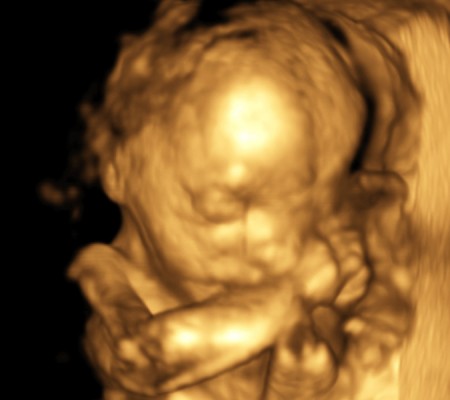

3D i 4D tehnologija omogućava da vidimo površinu bebe na lepši način i pokrete ploda u realnom vremenu.

Takođe nam omogućava da bolje vidimo fetalne mane na licu, šakama i stopalima.

Kao i 2D, 3D i 4D koriste ultrazvučni talas da se kreira slika bebe u materici. 3D je kreirana slika u prostoru dok 4D prikazuje pokret unutar materice pa možemo videti kako se beba smeje, mršti ili zeva.

Da bi se dobile dobre slike poželjno je da se pregled radi između 24 i 32 nedelje trudnoće.